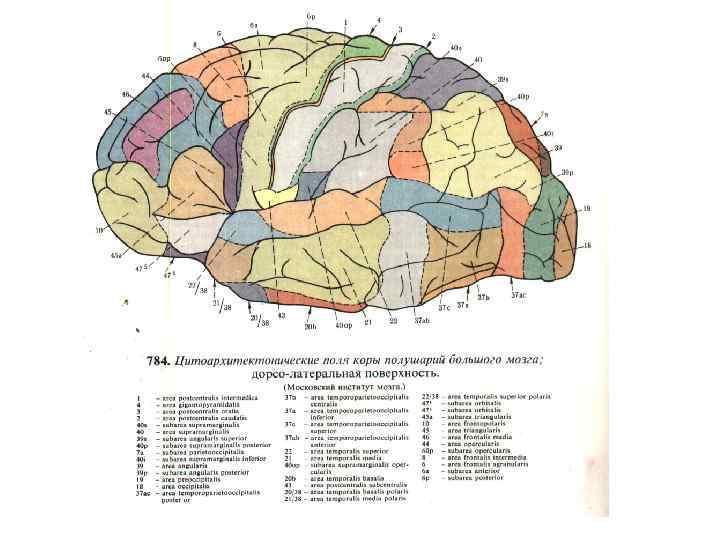

Схема чувствительных зон новой коры мозга